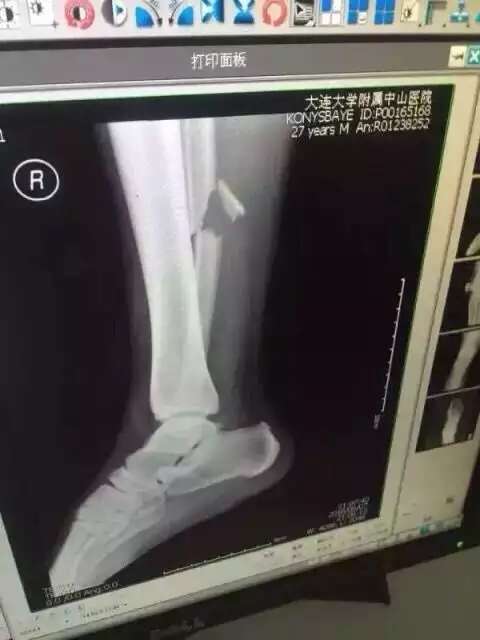

Инцидент случился на 45-й минуте матча, который проходил в Даляне. За него Хан получил предупреждение, а Конысбаев в результате инцидента получил ужасную травму. Прямо с поля полузащитник был увезен на машине "скорой помощи" в больницу, где ему сделали операцию.

Фото со страницы пользователя Facebook Сержана Касена